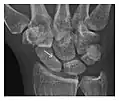

High-energy trauma fractures

Figure 3: A 26-year-old man presenting with wrist pain after being assaulted. (a) Initial anteroposterior radiograph shows a subtle linear lucency within the scaphoid extending to the scaphocapitate articular surface that was overlooked (arrow). (b) Initial "scaphoid" view was negative. (c) Followup anteroposterior radiographs, 12 days later, shows obvious scaphoid fracture (arrows).[1]